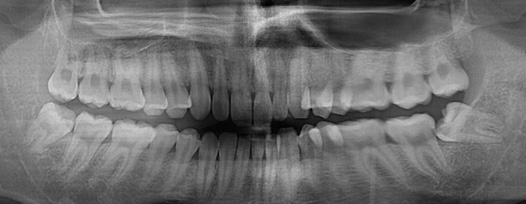

청담네오플란트는 3D CT 촬영 후 전문의료진들의 정확한 분석으로 안전하게 사랑니를 발치합니다.

청담네오플란트치과 사랑니 발치 프로세스

01. CT 촬영

안전하고 통증을 최소화한 발치를 위해 3차원 정밀 분석을 합니다.

02. 정확한 분석

사랑니의 크기와 방향, 깊이, 뿌리 상태 등과 구강검진을 실시합니다.